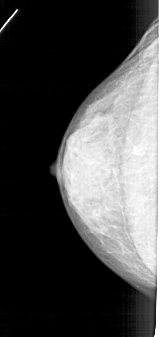

A_1352_1.LEFT_MLO

LEFT_CC LINES 4711 PIXELS_PER_LINE 2236 BITS_PER_PIXEL 12 RESOLUTION 43.5 NON_OVERLAY